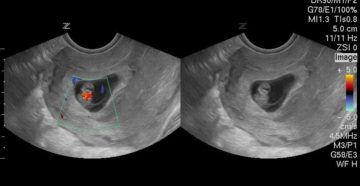

Что нужно знать о сердцебиении у плода Врачи следят за сердцебиением плода на протяжении всего…

Болезненные ощущения в яичниках при беременности Многие женщины отмечают, что у них болят яичники при…